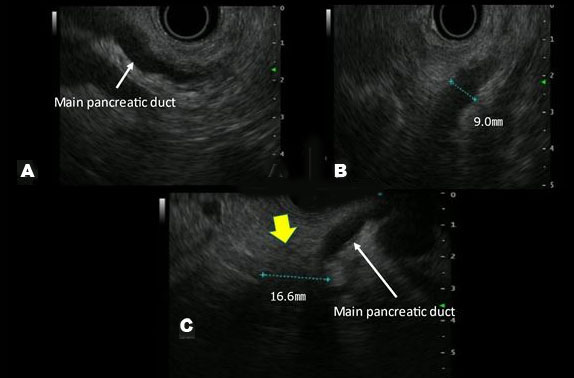

A blood test revealed increases in HbA1c and carcinoembryonic antigen to 11.2% and 8.7 ng/mL, respectively. Abdominal ultrasonography and Sonazoid® (Daiichi-Sankyo, Tokyo, Japan; GE Healthcare, Milwaukee, WI, USA) enhanced ultrasound (Figure 1) did not reveal a hypoechoic figurine indicative of pancreatic cancer on the pancreatic head side of the dilated main pancreatic duct. In the horizontal-section image of the contrast-enhanced CT arterial phase (Figure 2), a tumor suspected to be typical of pancreatic cancer that was contrasted late on the pancreatic head side of the interrupted main pancreatic duct, could not be recognized. In the coronary image (Figure 3), the pancreas was atrophied from the body to the head and there was dilation of the main pancreatic duct, revealing prominent fatty change in the pancreatic body; however, no neoplastic lesion was detectable (Figure 4). Endoscopic ultrasonography (EUS) revealed dilation of the main pancreatic duct and atrophy of the pancreas as on the abdominal ultrasonography; nevertheless, the tumor could not be clearly visualized. Therefore, histological diagnosis using endoscopic ultrasound-guided fine-needle aspiration (EUS-FNA) was considered difficult. Hence, we decided to conduct a detailed examination using other modalities.

Figure 4: Images of the pancreatic body (A and B) and pancreatic head (C) via endoscopic ultrasonography (EUS) are shown. The main pancreatic duct dilated to 9.0 mm, as in AUS. Observation of the pancreatic head from the duodenum revealed a slightly irregular hypoechoic area (yellow arrow), which could not be clearly visualized as a tumor. In addition, the reproducibility of the images was low, suggesting the possibility that the images exclusively captured changes in chronic pancreatitis.